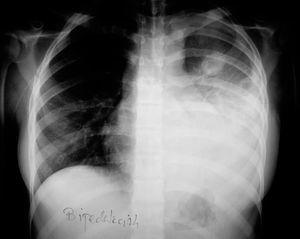

En la radiografía y tomografía axial computarizada (TAC) de tórax (figs. 1 y 2) se apreciaba una imagen redondeada y cavitada en lóbulo superior izquierdo, con un extenso derrame pleural del mismo lado.

Figura 1. Radiografía de tórax: se observa colección pleural izquierda asociada a condensación con broncograma aéreo en lóbulo inferior izquierdo. Nódulo cavitado en lóbulo superior izquierdo.